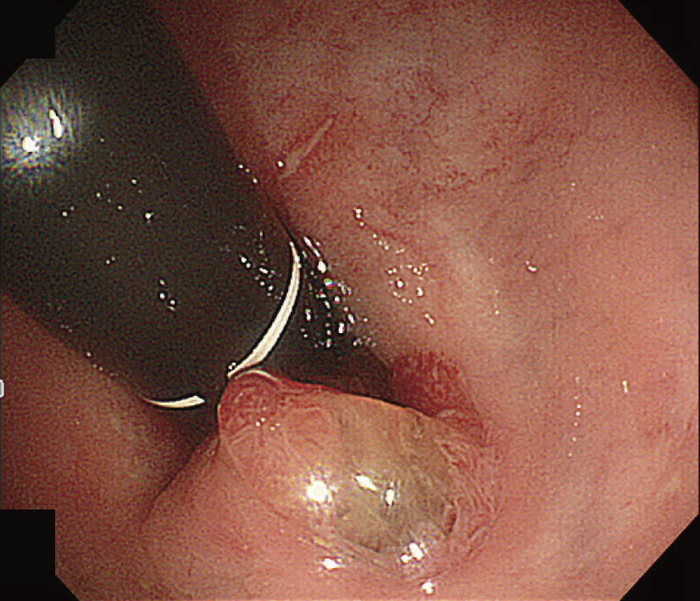

内視鏡検査による存在診断における課題は,CD関連消化管腫瘍を疑う所見の拾い上げになる。直腸肛門管領域に絨毛様の表面構造を有する病変を認めることが多い(図26)が,分化度の低い病変の拾い上げに有用な内視鏡所見はわかっていない1,3)。特に内科的治療で炎症の消退が困難な慢性に炎症が持続する領域の場合,炎症により腫瘍性病変を疑う所見の拾い上げがさらに困難となる。

図26 痔瘻一次口から表出したクローン病関連腫瘍の直腸反転内視鏡観察像

粘液をともない,腫瘍性病変を強く疑う表面構造を有している。当初の生検病理診断は過形成性病変で,再検の後,直腸切断術を施行した。(文献1)から転載)